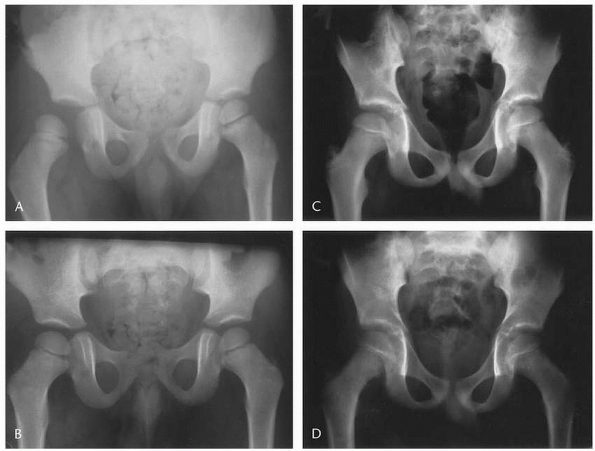

position that best aligns the bone (Fig. 21-10A,B).

intraoperative positioning (Fig. 21-10C,D).

| FIGURE 21-10 A. A 4-year-old boy fell from his window, causing a displaced type IV. B. Positioning of the hip in a spica cast is usually in hip flexion and confirmed under fluoroscopy. C. Fluoroscopic radiographs in 90 degrees of hip flexion insure anatomic correctness. D. At 1-week follow-up, radiographs were inconclusive; a CT scan assists in confirming location. |